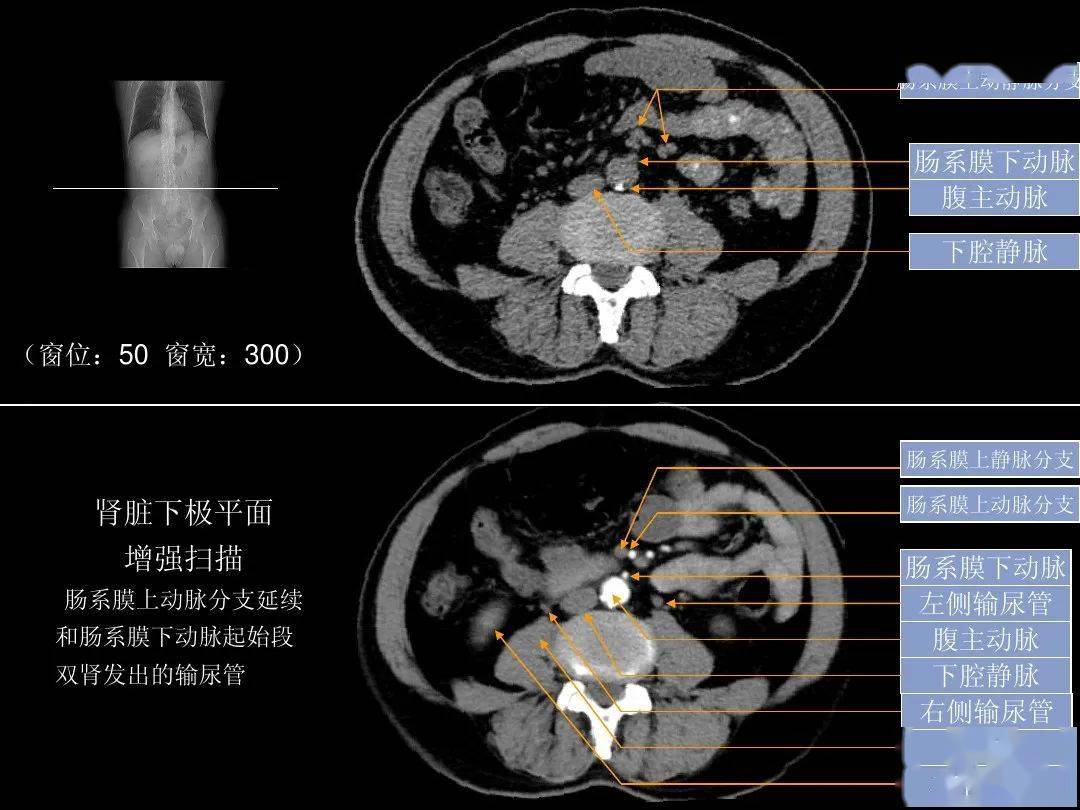

「腹部ct断层解剖」腹部ct扫描横断位解剖 详细标注,值得收藏